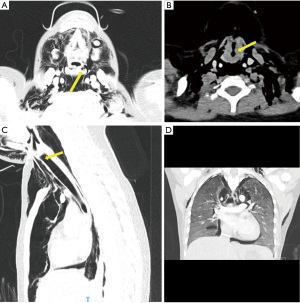

Given her extensive air leaks and history of significant retching, there were concerns for esophageal perforation secondary to drug-induced esophagitis or Boerhaave syndrome (11,12). Computed tomography (CT) neck and thorax did not find definite esophageal perforation, but revealed widespread pneumomediastinum, bilateral pneumothoraces, lower cervical and thoracic subcutaneous emphysema with suggestion of a tear in the left hypopharynx and anterior wall of the upper trachea. There were diffuse pulmonary ground-glass changes involving the entire lung with an apico-basal gradient (Figure 2).